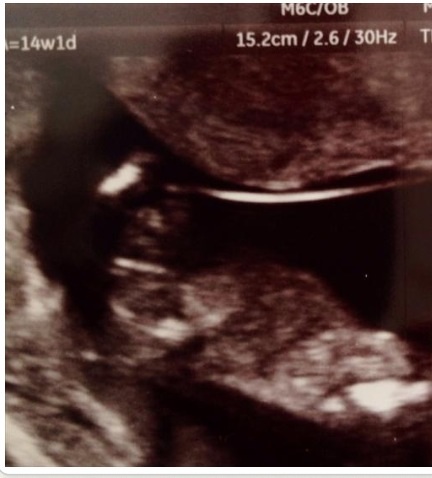

Attachment 18523

I think boy? But I really suck at potty shots!

14+1